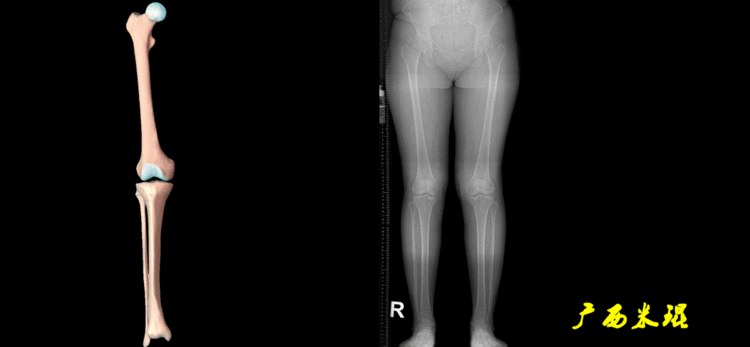

2、画出下肢的轴线确定髋关节、膝关节、踝关节的中心点后,我们才能了解下肢的几个轴线。(1)解剖轴股骨和胫骨的骨干中线为解剖轴,股骨解剖轴和胫骨解剖轴的夹角正常值为174°±1°。

(2)机械轴机械轴是连接近端和远端关节中心点的直线。

机械轴要分前后位及侧位,站立前后位(也就是冠状面)股骨头中心与踝关节中心的连线通过膝关节中心,这是下肢的机械轴线,也就是下肢力线,常说Mikulicz线。冠状面的力线评估在临床工作中最常用、最基础、最重要。

站立侧位(矢状面)股骨头中心与踝关节中心的连线也通过膝关节中心,这也是下肢的机械轴线,这也是下肢力线。

矢状面的下肢力线常常被医生忽视,其实它的改变也是膝关节疼痛的常见原因。